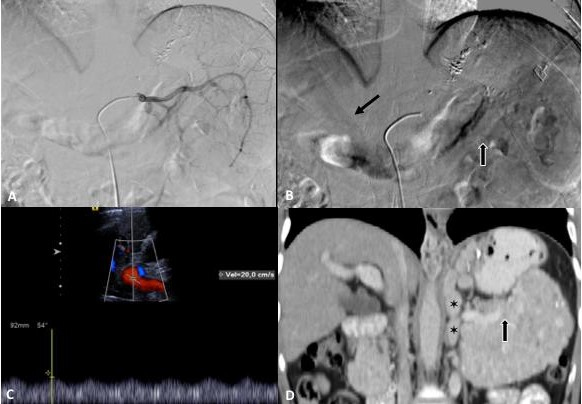

Por ultrasonido se demostró parénquima hepático normal y páncreas con aumento de volumen y ecogenicidad heterogénea. Por tomografía multifásica el páncreas mostró aumento de volumen en su totalidad, precontraste densidad heterogénea con zonas nodulares hiperdensas y calcificaciones, con atenuación promedio de 45UH, realce arterial con atenuación de 86UH, portal 112UH y disminución en fase venosa a 100UH. Además se observó colapso de la porción distal de la vena esplénica y circulación colateral en hilio esplénico, fondo gástrico y periesofágica (Fig. 1 y 2). La medición de gradientes hepáticos y angiografía de tronco celíaco con presión de vena suprahepática libre 12mmHg, presión enclavada 14mmHg, gradiente de 2mmHg, sin evidencia de shunts intrapancreáticos, hallazgos consistentes con hipertensión portal postsinusoidal (Fig. 2).